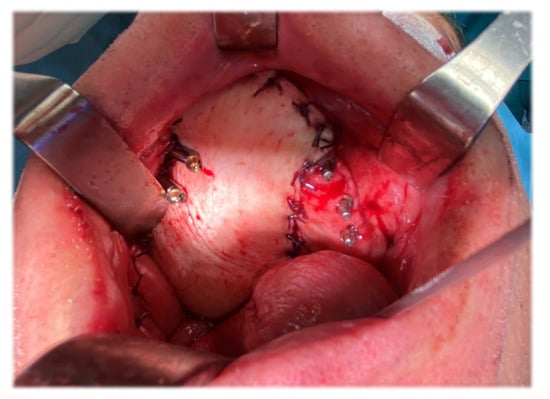

Figure 13 shows an intra-oral view of the patient showing reconstruction with the vascularized right ALT flap. The antero-lateral thigh revascularized soft tissue flap was placed medially to the zygomatic implants and was sutured to the margins of the resection, as can be seen in Figure 13. As a result, the smooth body of the implants were surrounded by cheek mucosa on the lateral aspect, and the soft tissue flap on the medial aspect.

Figure 13.

Intra-oral view of the patient showing reconstruction with vascularized right ALT flap. [Note: the reconstruction of a much larger area than the preoperatively planned resection (due to presence of neoplastic tissue in the left nasal cavity) with the remaining dental implants on left maxillary side #23, #25, #26].